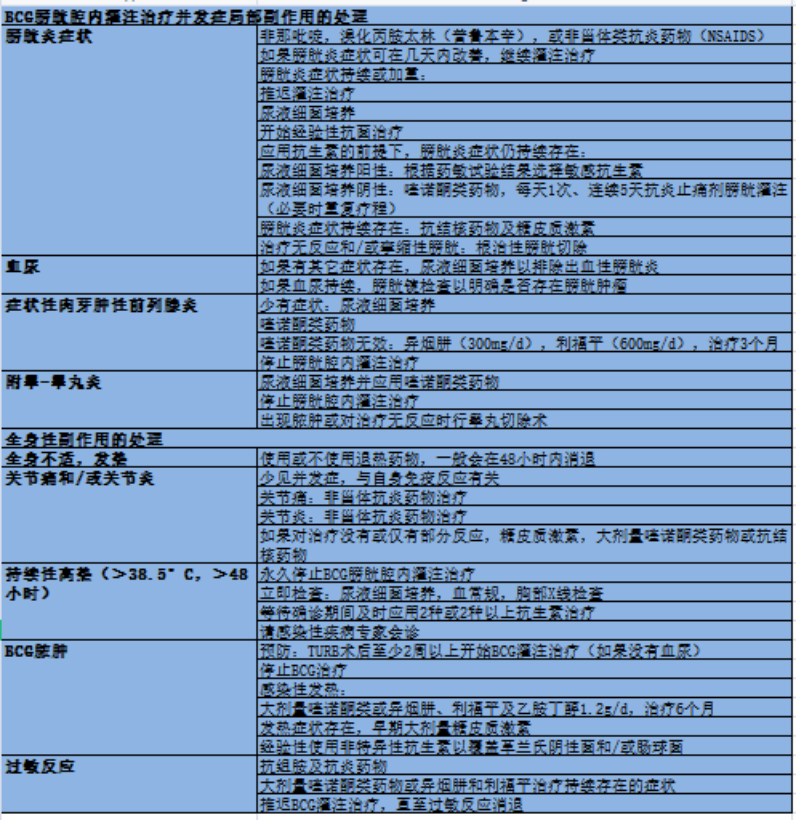

目前肌层浸润性膀胱癌的标准治疗方案为膀胱癌根治术+淋巴结清扫术,保留膀胱方案主要为经尿道膀胱癌电切术+术后卡介苗(bacilli calmette guerin,BCG)膀胱灌注。

BCG治疗期间或治疗后复发低级别肿瘤,不属于BCG治疗失败。

BCG膀胱灌注治疗失败病例分类: